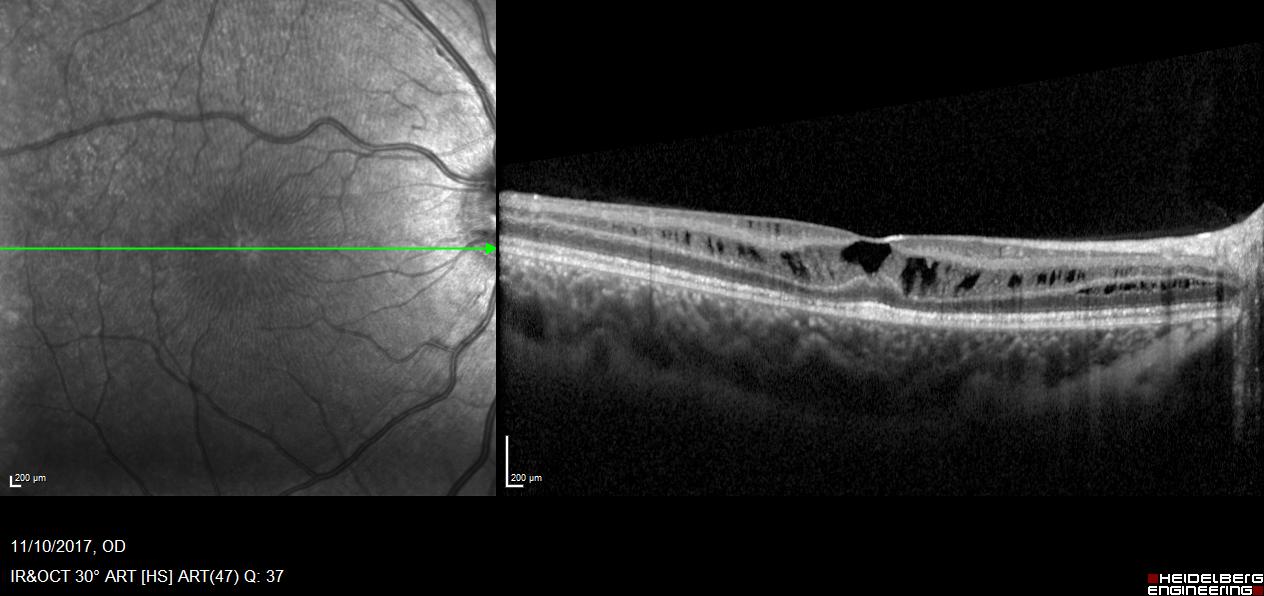

Η συγγενής φυλοσύνδετη ρετινόσχιση είναι μια κληρονομούμενη δυστροφία του αμφιβληστροειδή η οποία οφείλεται σε μεταλλάξεις του γονιδίου RS1. Εμφανίζεται με μείωση της κεντρικής όρασης σε νεαρούς άρρενες. Ο ηλεκτροφυσιολογικός έλεγχος (Ηλεκτροαμφιβληστροειδογράφημα) είναι πολύτιμος για τη διάγνωση της νόσου μιας και έχει χαρακτηριστικά ευρήματα στις καταγραφές ενώ ο γενετικός έλεγχος ταυτοποιεί τη διάγνωση.